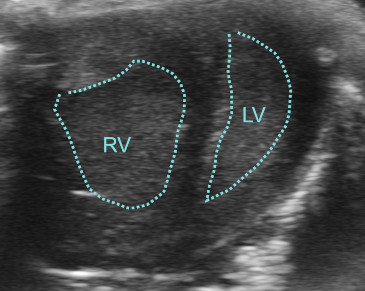

Introduction: The capacity of the left ventricular (LV) neonatal myocardium for adaptive regeneration following injury or pressure overload has been widely recognized. However, it is unclear whether the right ventricular (RV) myocardium has similar plasticity and how injury and regenerative response of one ventricle influences the other ventricle. While, in adults, LV pathologies account for the majority of cardiovascular disease burden, persistent pulmonary hypertension and the resulting RV pressure overload of varying degrees is a common symptom in neonatology that may lead to severe disease or even death. In contrast, surgically induced elevation of RV pressure by pulmonary artery banding has been shown to enhance LV function in young children with dilated cardiomyopathy often preventing the need for transplantation. Although its molecular mechanisms remain unknown, this observation indicates great plasticity of the RV and the existence of ventricular crosstalk shortly after birth. To investigate RV plasticity and regenerative potential and to explore the molecular mechanism of “interventricular” effects in the neonatal phase, we established a neonatal murine model of pulmonary artery banding to induce pressure overload on the RV as early as postnatal day 1 (P1). Methods: For the surgery we used wild-type CD1 mice on P1. Anesthesia was induced by isoflurane and maintained by hypothermia during the surgery. After opening of the chest, the main pulmonary artery (MPA) and aorta were carefully separated. A suture was placed around the base of the MPA (Figure 1) and then tied around a placeholder needle, constricting the lumen of the MPA to fit the needle’s size. After removing the needle, the chest and skin were closed and the mouse was rewarmed. After full recovery, it was placed back in the mother’s cage. Before surgery and 6h thereafter, analgetic treatment with buprenorphine was administered. Echo was performed on P7 and P14 to confirm the correct positioning of the constriction and to assess RV and LV function. Results: Echocardiography confirmed a persisting constriction of the main pulmonary artery with doppler flow measurements showing a markedly increased velocity in the MPA. Consequently, the RV was thickened and the septum was deviated to the left (Figure 2). Post-mortem anatomic inspection on P14 confirmed RV and right atrial enlargement with additional signs of central venous congestion, such as enlarged liver and kidneys. Discussion: We successfully established neonatal pulmonary artery banding in P1 mice and confirmed the desired hemodynamic effects by echocardiography and anatomic inspection. In further work, we will determine the needle size that can raise an adaptive response of the RV to pressure overload without causing decompensated RV failure. This new neonatal surgical model will enable us, for the first time, to gain insight into the plasticity of the neonatal RV and understand molecular mechanisms of myocardial adaptation to RV pressure overload and ventricular crosstalk. Therefore, this study will pave the way towards a better understanding of cardiac plasticity to identify novel therapeutic targets for patients, especially children with cardiovascular disease. Figure 1 Intraoperative view. 1: MPA, 2: aortic arch, 3: ductus arteriosus (obliterated) Figure 2 Short axis view on P14. RV: Right Ventricle, LV: left ventricle |